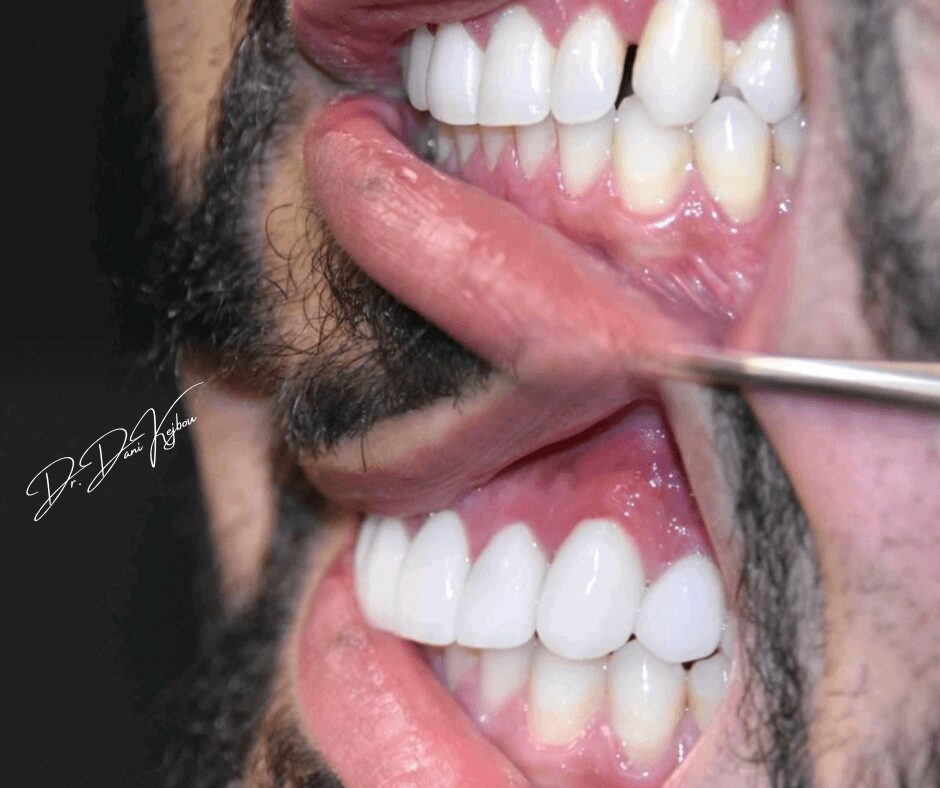

Dental school allows me to join my two passions into one, that being science and artistry. Ultimately leading me to the life of cosmetic dentistry.

My dental office is located in Bloomfield hills Michigan, Bloomfield hills dental associates. I provide all aspects of dentistry, from braces, fillings, and extractions. But my main focus is cosmetic and implant dentistry. What sets me apart is my compassion for my patients needs and the ability to provide and deliver their dream results. Having an artistic mind allows me to show what each individual can expect before they even begin their transformations.